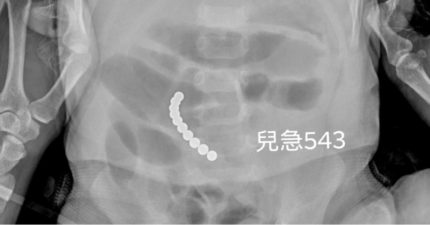

2歲童「肚內卡10顆珠珠」狂吐18次 媽驚吐:姐姐在玩

April 12, 2022

台灣